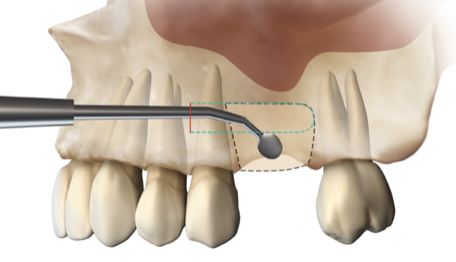

After the 3rd bone graft failed, the patient sought second opinions. She was a college sophomore at the time. Using a combination of interdisciplinary therapies, including S.M.A.R.T. minimally invasive bone grafting, Dr. Ernesto Lee was able to tridimensionally reconstruct this severe defect and place implants to restore the patient’s smile. The S.M.A.R.T. bone graft was also extended to treat adjacent teeth with thin/dehisced bone.

S.M.A.R.T. MINIMALLY INVASIVE BONE GRAFTING